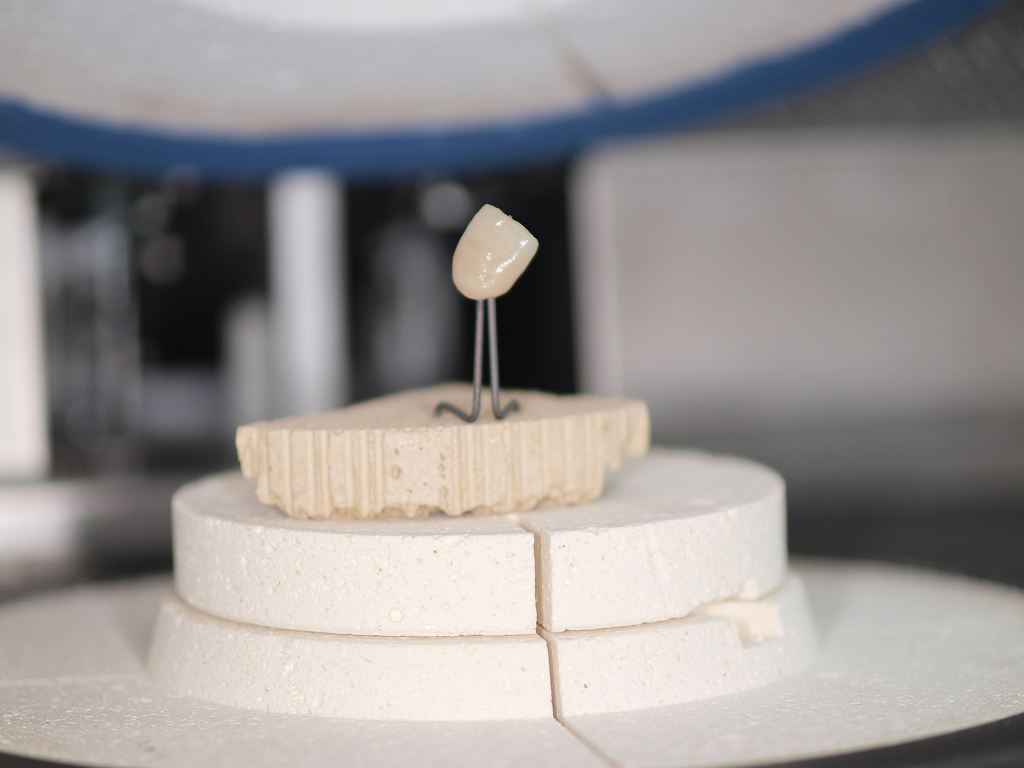

前歯部のセラミッククラウンにはジルコニアクラウンとオールセラミッククラウンの2通りが存在します。 オールセラミッククラウンはe-maxといわれるイボクラ社のガラス系二ケイサンリチウムをフレームとして使用していき、レイヤリングの形態をとります。|お知らせ |広島市安佐南区の歯科医院

前歯部のセラミッククラウンにはジルコニアクラウンとオールセラミッククラウンの2通りが存在します。 オールセラミッククラウンはe-maxといわれるイボクラ社のガラス系二ケイサンリチウムをフレームとして使用していき、レイヤリングの形態をとります。

前歯部のセラミッククラウンにはジルコニアクラウンとオールセラミッククラウンの2通りが存在します。 オールセラミッククラウンはe-maxといわれるイボクラ社のガラス系二ケイサンリチウムをフレームとして使用していき、レイヤリングの形態をとります。